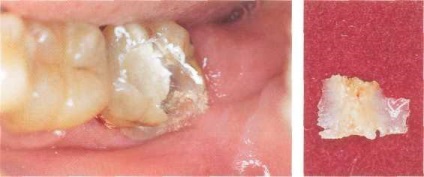

10 nap után a rendelkezés a nem-turn-down fogápolás a beteg fordult az on-shu klinika nélkül Ms-homlokát. Az üreg bal alsó második moláris már kinyílt, és tele van egy ideiglenes tömés. A régióban ez fog jelölni vérbőséget és a fogíny duzzanata miatt ödéma.

Ábra. 42. utáni állapot devitalization cellulóz.

Eltávolítása után az ideiglenes tömítések (pre közgát szabtak) torkolatában a gyökérkezelés volt észlelése felesége sötétszürke devitaliziruyuschaya paszta. Az üreg alján volt a fogszuvasodás.